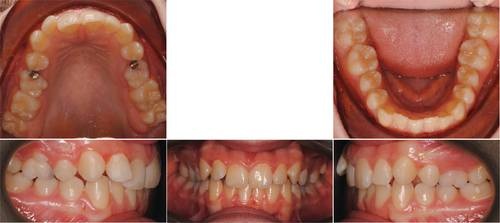

Ruby, a 14-year-old female patient, presented with crowding of the upper incisors, Class II malocclusion, over-retained primary second molars, a midline discrepancy, and narrow arch forms (Figs. 1–3). We initiated treatment using the LightForce system, combined with remote monitoring through DentalMonitoring.

Traditionally, a comprehensive case like this would have required 18 to 24 months of treatment and frequent in-office visits to guide wire progression and track dental development. Instead, we used DentalMonitoring Goals to take a more proactive and responsive approach (Fig. 4). We monitored for archwire passivity to determine optimal timing for wire changes, tracked the loss of deciduous teeth, and set Class I canine relationship as a defined endpoint.

Instead of following the traditional path of four-to-eight-week appointment intervals, we maintained weekly oversight through DentalMonitoring, scheduled only eight in-office appointments, and, in some phases, extended visit intervals to as much as 16 weeks (Fig. 5).

Ruby’s journey reflects the clinical precision, scheduling flexibility, and patient-centered efficiency that become possible when digital tools are used not just for convenience, but with intention (Figs. 6–8).